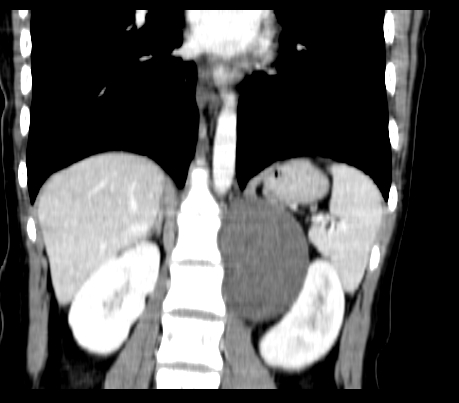

静脉期

延时5分钟